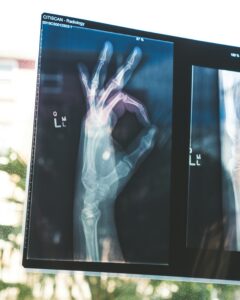

Det bästa med att bli sjuk är att man får bli frisk igen! Kom gärna till oss på Vårdcentralen när du är sjuk så vägleder vi dig till återfrisknande.